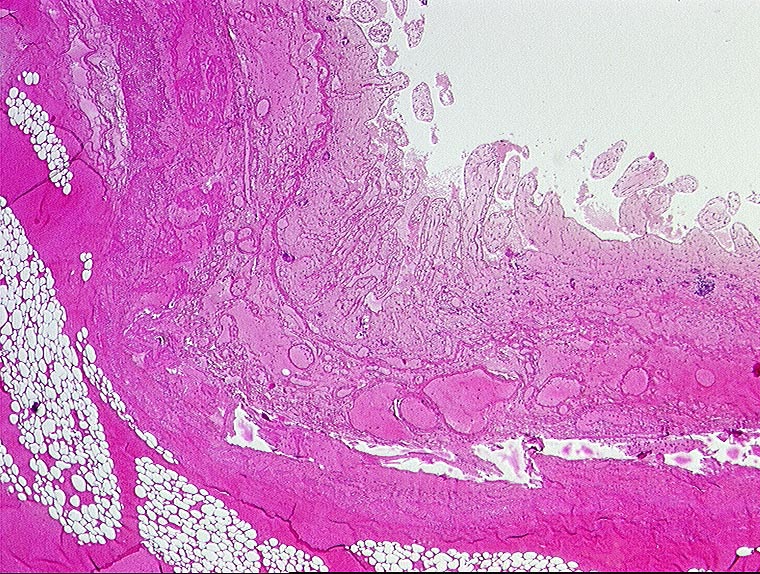

embolischer Mesenterialinfarkt

Hämorrhagische Nekrose der Darmwand.

Alter Myokardinfarkt Parietalthrombus. Frische Emboli in eröffneten Ästen der Arteria mesenterica superior.